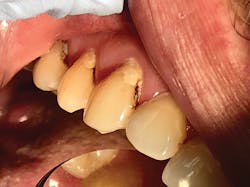

Adverse effects of SDF are rare and mostly limited to the dark brown or black staining that occurs when SDF contacts a carious lesion. SDF will not stain healthy tooth structures. Contraindications include patients with allergies to heavy metals (specifically silver or fluoride allergies), ulcerative gingivitis, or stomatitis; those undergoing thyroid gland therapy; and on teeth that show signs and symptoms of irreversible pulpitis.

We use SDF in our office as an alternate treatment option for medically challenged patients and older adults. As our heavily restored older patients become more restricted in their ability to perform daily hygiene routines, such as brushing teeth and flossing, we start to see more marginal and root surface caries. The cause of this can be twofold: lack of proper plaque removal and poor diet. When interviewing patients in this age group or their caregivers, we find patients tend to experience dry mouth and often find relief from sipping on sugary beverages or sucking on hard, sugary candies. In a dry mouth, these habits accelerate tooth decay. Compromised medical situations often prevent patients from undergoing dental treatment.

As dental providers, it is our responsibility to educate patients and their caregivers and provide treatment options. For a patient who is in the last stages of dementia, it is neither ethically nor morally appropriate to put them through extensive restorative procedures or extractions. In our office, we place SDF at the initial diagnosis of decay after removing food debris and plaque, and then we reapply it at subsequent appointments. If the caregiver requests, we can follow up with treatment at the assisted living facility. SDF shows success with annual applications, but in our practice, we have seen greater benefits if SDF is reapplied at six-month intervals during the first two years. We attribute this to the difference in home-care plaque removal, habits, and diet, which are often uncontrolled in real-life situations, as compared to clinical trials.